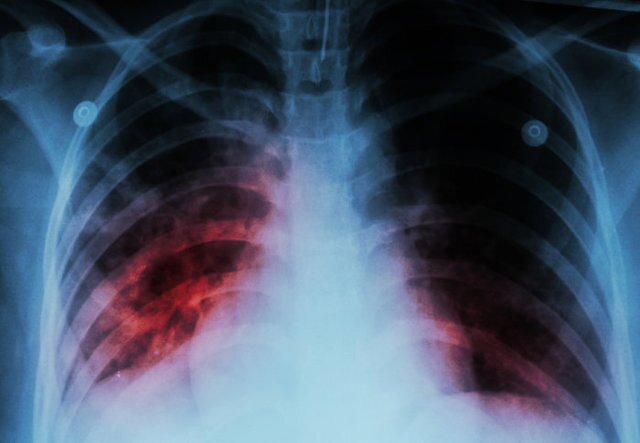

دکتر مهشید ناصحی  با اشاره به شعار امسال روز جهانی سل مبنی بر "مشارکت همه جانبه جامعه، مسیر مطمئن برای دستیابی به حذف سل"، گفت: سل یک بیماری عفونی واگیر است که در اثر میکروبی ایجاد می‌شود که می‌تواند به هر قسمتی از بدن انسان مانند استخوان‌ها، مفاصل، مغز، کلیه، پوست و ...حمله و آن‌ها را گرفتار کند، اما به دلیل نیاز و علاقه زیاد این میکروب به اکسیژن، در ۸۰ درصد موارد ریه‌ها را هدف حمله خود قرار می‌دهد.

سل ریوی؛ شایع‌ترین نوع بیماری

وی افزود: با توجه به علاقه زیاد میکروب سل به ریه‌ها، شایع‌ترین نوع بیماری، سل ریوی است که افراد مبتلا معمولا علائمی نظیر سرفه مداوم (به مدت۲ هفته یا بیشتر) دارند که این سرفه‌ها می‌تواند با خلط همراه باشد یا نباشد، تب، کاهش وزن، تعریق شبانه، بی‌اشتهایی، خستگی زودرس و ضعف عمومی و گاهی در مواردی که بیماری دیر تشخیص داده می‌شود درد قفسه سینه، تنگی نفس و خلط خونی دارند.